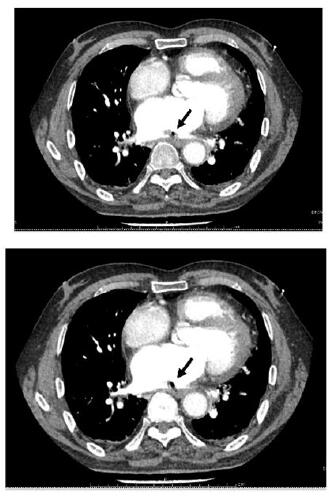

| 不同层面内左心房内低密度影,考虑心房食管瘘后气体残留,周围有血栓形成(黑色箭头示) 图 2 患者胸部增强CT结果 |

1 资料与方法患者,男,68岁;因“间断胸闷心慌1个月余,呕血伴发热1 d,意识障碍12 h”收入华中科技大学同济医学院附属同济医院。患者一个月前自觉胸闷、心慌,至当地市级医院诊断为“房颤、冠状动脉粥样硬化”,入院前34 d行房颤消融术+冠脉造影术,术后口服达比加群酯110 mg 2次/d,术后3 d再次因胸闷心慌至当地县人民医院住院治疗,给予对症治疗,症状可缓解。入院2 d前再次出现胸闷心慌等不适,入院前1日下午4时呕血约300 mL,伴寒战高热,最高可达39.5 ℃,并于入院当日中午12时出现意识障碍,言语不清,为求进一步治疗转至本院急诊科。急查头部CT示:脑萎缩,脑白质病;右侧半卵圆中心及左侧基底节区片状低密度影,考虑为缺血梗死灶;右侧小脑半球片状低密度影,考虑脑梗死、软化灶形成。后患者意识障碍较前缓解,急诊科收治入院。既往史:高血压史十余年,5年前脑梗死病史,10年前行腰椎间盘突出手术治疗,吸烟30余年,每日一包,饮酒30余年,每日250 mL,戒酒10年。入院体格检查:患者意识清醒状态,言语沟通不畅,心电监护提示:血压105/80 mmHg,脉搏87次/min,SPO2 100%,心率18次/min;双侧瞳孔等大等圆,直径2.5 mm,对光反射存在,双肺呼吸音粗, 未闻及啰音;心音可,律齐,未闻及杂音;腹软,移动性浊音阴性,肠鸣音正常。四肢无畸形,四肢活动无障碍,双下肢无水肿,生理反射存在,双侧巴氏征阳性可疑。患者入院后完善相关检查。血常规:白细胞计数23.23×109/L,血红蛋白93.0 g/L,血小板计数117.0×109/L,谷丙转氨酶14 U/L,谷草转氨酶17 U/L,尿素15.93 mmol/L,肌酐103 μmol/L,葡萄糖10.84 mmol/L,N-末端脑利钠肽前体(N-terminal pro brain natriuretic peptide,NT-proBNP)5 577 pg/mL,降钙素原32.51 ng/mL,高敏心肌肌钙蛋白I 413.9 pg/mL,血乳酸2.22 mmol/L。心脏超声检查示左房扩大55 mm,心脏收缩力下降,左心EF值40%。患者入院后给予抗感染、抑酸、营养支持等治疗,患者于入院当晚9时出现剧烈咳嗽,后意识障碍再次加深,遂行颅脑CT检查,示左侧大脑内气体栓塞(图 1);神经内科会诊,考虑脑内气体栓塞。给予患者头低脚高位,降低颅内压等治疗,次日晨复查胸部增强CT,示左房改变,考虑左房破食管瘘并左房血栓形成(图 2),诊断为“心房食管瘘”,请胸外科会诊意见:患者颅脑内积气吸收后,可进行心脏食管手术。患者于入院第2天上午8时出现呼吸衰竭,行气管插管术,呼吸机辅助呼吸,患者家属于当日下午因个人原因办理出院。

目前AEF疾病诊断较困难,主要体现在以下三个方面。首先,患者的发病时间区间大,有文献报道相关症状出现平均为术后19.3 d,最短为术后6 d,最长可以达到术后59 d[3],这可能与食道溃疡形成需要一定时间有关,本例患者明显的消化道出血出现在术后33 d,发病时间较晚,极易忽略症状与手术间的联系。其次,由于患者发病机制可导致临床表现不具有特异性,可出现胸部不适、呼吸困难症状,也可能出现呕血、意识不清等症状;目前文献报道常见临床症状主要集中在术后2~4周内(42%),主要症状表现为发热(73%)、神经系统症状(72%),消化道症状(41%)[5]。本例患者术后出现胸部不适症状,外院反复检查治疗,无明显改善,后患者出现呕血、高热、意识不清,复查头颅CT发现气体栓塞,排除深静脉穿刺等有创操作后,最后通过胸部增强CT明确诊断,整个诊断过程比较曲折。因此需要急诊特别是专科医生加深对该疾病的认识。此外,AEF目前检查方式主要包括胸部平扫或增强CT、胸部MRI[7]、食管X线造影、心脏超声、食管胃镜检查等,其中胸部CT平扫或增强CT是首选检查方式,必要时可反复检查,本例患者最终通过胸部增强CT明确诊断,主要表现为左心室气栓并血栓形成。而需要注意的是部分患者行食管胃镜检查可使病情明显加重,当怀疑该疾病时应当避免该检查,同时食管X线造影或经食道超声也应尽量避免。部分地区缺乏相应的检查手段或时间条件受限,使得部分危重患者失去诊断机会,因此临床上对于房颤射频消融术后新出现感染表现和消化、神经系统等症状的患者需要高度重视,积极选择合适的检查方法以明确诊断。